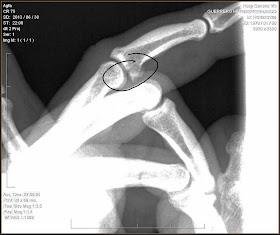

Radiografía realizada 4 meses más tarde

Llega el día de la visita a Neus y al Traumatologo, me hace una radiografia depus de hablar un montón de rato y explicarle todo lo anterior, como me sentía lo que yo notaba en mi dedo cuando me accidente, etc, me mira, se hecha las manos a la cabeza y pone la radiografía en la pantalla, me lo quiere explicar de seguida, le digo "esta roto, ya lo veo", me mareo, me entra un sudor frío y sentí mucha rabia, llore, de impotencia de ver que hacía cuatro meses que tenía el dedo roto y un gilipollas no había sabido o no se había preocupado de interpretar correctamente una radiografía, , se me cayo el mundo encima (20 min después me sacaban la muela del juicio), por mi cabeza paso de todo, el Trauma me dio varias soluciones.

Radiografia del día del accidente (diagnosticaron que no estaba roto)

Efectivamente y como creía mi abogado el dedo se veía roto y un medico inútil, energumeno y mil adjetivos mas que se me ocurren no detecto en origen que mi dedo estaba roto, si aquella noche, aquel diagnostico hubiese sido de mi dedo roto, a día de hoy esto solo sería una anécdota, me lo hubiesen inmovilizado el tiempo necesario y se hubiese soldado mucho mejor que de cualquier manera, así que ahora estamos inmersos en un ir y venir al hospital para hacer valoraciones, ellos quieren untarte de dinero por la negligencia (poco porque ese dedo no tiene demasiado valor, según los cánones de hoy en día) y yo pido mucho más, mas que nada unas disculpas, solo el que siente la escalada como parte de su vida me podrá entender